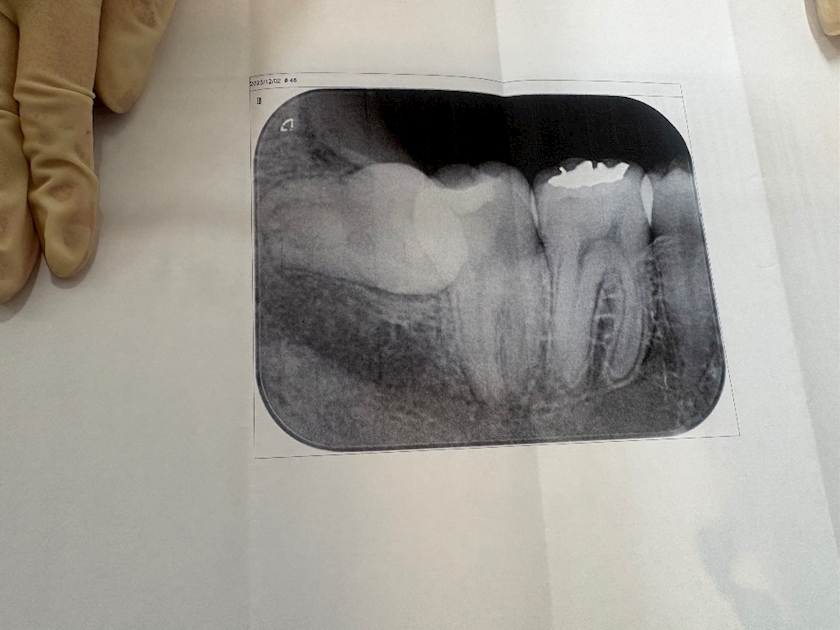

いくつになっても抜歯は恐怖でしかない。でもこの生え方の方がもっと恐怖でしかない

親知らず真横に埋まって

生えてた🤣🤣

これは抜かないとダメだねって言われて

大きな病院に紹介状

出されました😃

入院して切開して

顎けずって抜くらしい🙃

確実に麻酔切れたら痛いし

腫れるらしい🙃